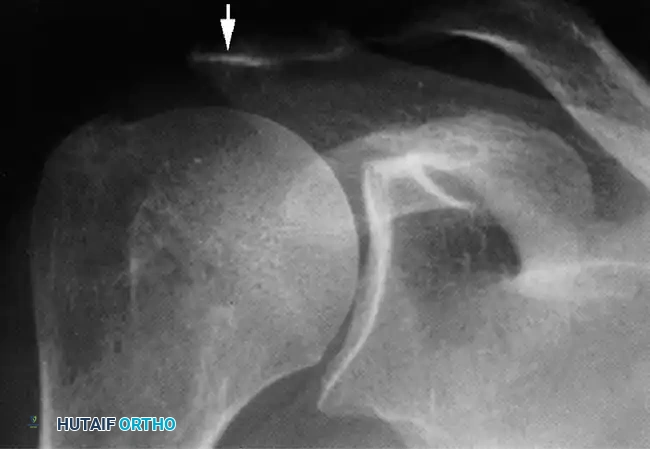

Associated Surgical & Radiographic Imaging